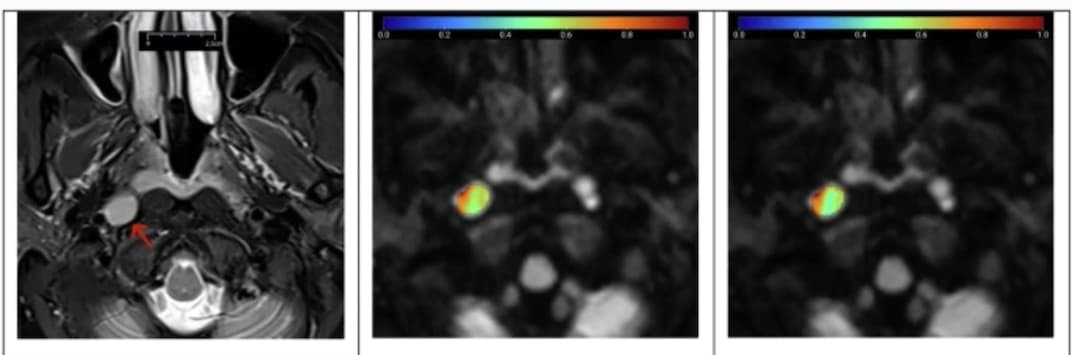

Distinguer les ganglions lymphatiques cervicaux bénins et métastatiques par IRM conventionnelle n’est pas facile. Une étude publiée dans la Revue European Radiology tente de différentier les ganglions lymphatiques bénins et métastatiques en combinant de nouveaux modèles d’IRM de diffusion et leurs c...